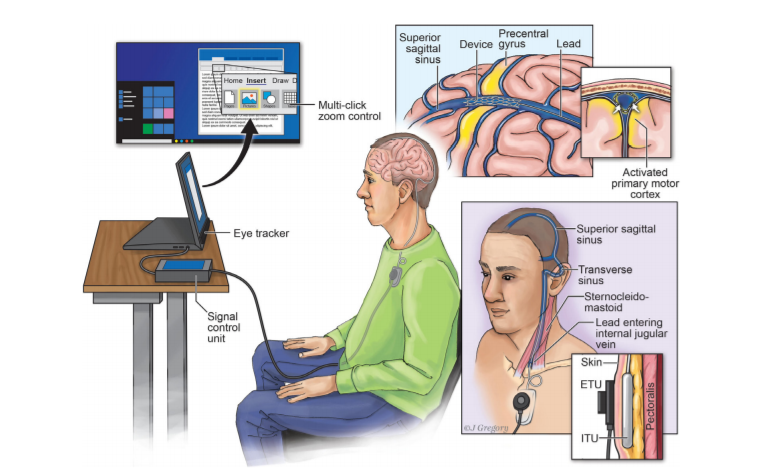

ALS,也被称为Lou Gehrig 's disease,已经导致62岁的奥基夫失去很多运动功能,并使他无法工作。2020年4月,他接受了Stentrode BCI,这是一种通过颈静脉植入大脑的小型支架安装电极阵列。

62 岁的 O'Keefe 因患有ALS,失去很多运动功能,无法工作。2020 年 4 月,他接受了 Stentrode BCI,这是一种通过颈静脉植入大脑的小型支架式电极阵列。

O’Keefe 说,“当我第一次听说这项技术时,我就知道它能给我带来很多的独立性,这个系统令人惊讶,就像学习骑自行车一样——需要练习,但是一旦你开始滚动,它就会变得很自然。”

“现在,我只需想我想点击电脑上的哪个位置,然后我可以发送电子邮件、银行、购物,现在还可以通过 Twitter 向全世界发送消息。”

两位患者植入后,借助这套脑机接口装置成功地进行日常的上网操作:比如发短信、发送电子邮件、线上购物和网上操作银行业务等。

借助脑机,两位患者还成功地操作了Window 10,并且每分钟可以打14个和20个字符。